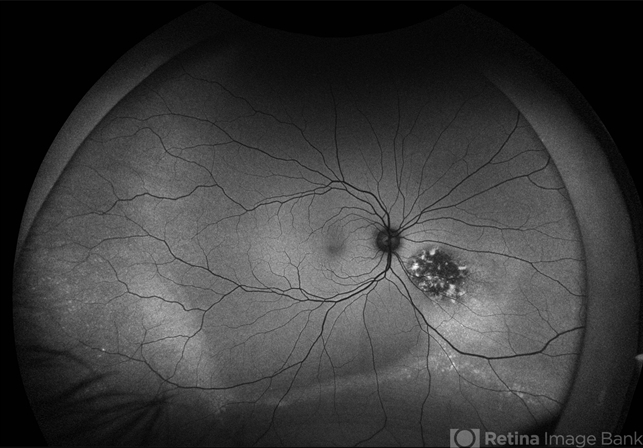

- amelanotic melanoma

- This FAF image reveals a hypoautofluorescent mass with areas of dense hyperautofluorescent stippling—a classic pattern suggestive of an amelanotic choroidal melanoma. Amelanotic melanoma is a rare variant of uveal melanoma, accounting for only a minority of cases. Unlike pigmented melanomas, these lesions lack melanin, making them more challenging to detect on conventional color fundus imaging. FAF Characteristics: • Central hypoautofluorescence: due to loss or compression of the RPE • Peripheral hyperautofluorescent speckling: consistent with lipofuscin accumulation or RPE disruption • Often associated with subretinal fluid or orange pigment seen clinically Location: Juxtapapillary, with potential optic nerve involvement—a factor that complicates both diagnosis and